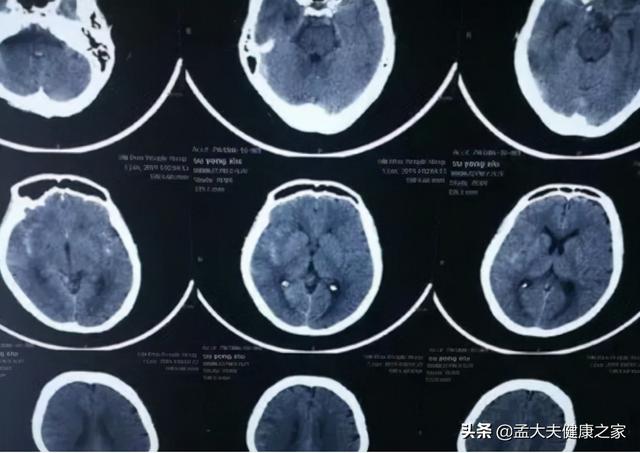

手术治疗.十二胃溃疡未及时治疗,等待病情发展到最后阶段,极有可能会造成癌变,引发胃癌.因此,在确诊之前,有必要去专科医院进行详细的胃镜检查。胃镜检查是目前检查胃健康最有效的手段,可以直接反映胃的最真实情况,为以后的治疗提供有利条件。

早期的胃癌患者可以在胃镜下进行病灶切除手术,从而保证了部分完整的胃部结构和胃功能。同时,胃部病灶切除术需要有一定的技术含量,建议患者去到大医院接受正规手术治疗,千万不要去资质差的医院诊治,以免造成不良后果。

除了胃镜手术外,常见的应是开腹手术。开腹手术包括了胃的切除,淋巴结清除和消化道重建几个环节。医生根据患者的肿瘤位置以及大小,有针对性的手术切除;另外,完成手术后患者是能够正常饮食的,不受手术影响。